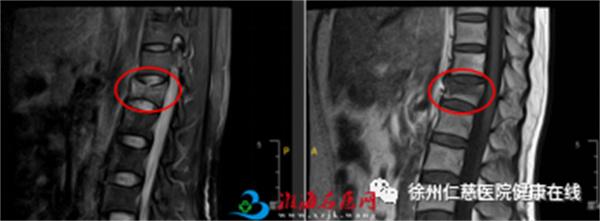

患者李某是一名50岁的女性,骑电车时被另一电动车撞倒,臀部着地,当时就感觉腰背部疼痛,活动受限。被家人送至当地医院拍片显示T12椎体骨折,为进一步治疗,患者被家属送到徐州仁慈医院急诊,以“T12椎体骨折”收治入院。

术前MR